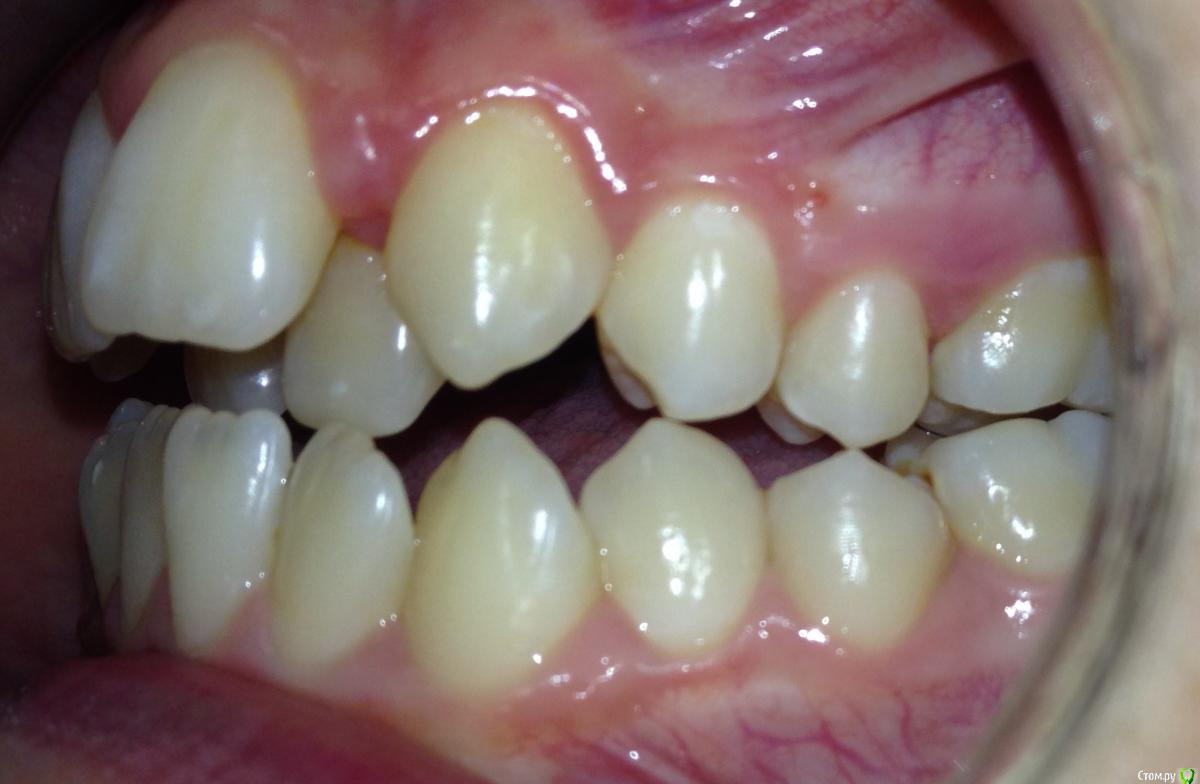

Алевтина Петровна Опубликовано 26 августа, 2015 Поделиться Опубликовано 26 августа, 2015 Всем добрый вечер. Я начинающий ортодонт. Надеюсь,что вы поможете с планом лечения. Пришел пациент. 13 лет. Ситуация по мне непростая, но очень интересная. Ссылка на комментарий

Алевтина Петровна Опубликовано 26 августа, 2015 Автор Поделиться Опубликовано 26 августа, 2015 Прикрепляю дополнительные фото, извините за качество. Это моя первая публикация, пытаюсь разобраться. Ссылка на комментарий

Molox Опубликовано 26 августа, 2015 Поделиться Опубликовано 26 августа, 2015 Ставьте Дерихсвайлера, вопрос с дефицитом места отпадет сам собой. И потом на брекетах по накатанной. 2 Ссылка на комментарий

Алевтина Петровна Опубликовано 27 августа, 2015 Автор Поделиться Опубликовано 27 августа, 2015 Смущало то, правильно ли я планирую лечение. Заказала аппарат дерихсвайлера, нет опыта его использования, вот и не знаю получу ли достаточно места. Спасибо большое за советы. С хирургом не работала, попробую на RPE. Спасибо еще раз Ссылка на комментарий